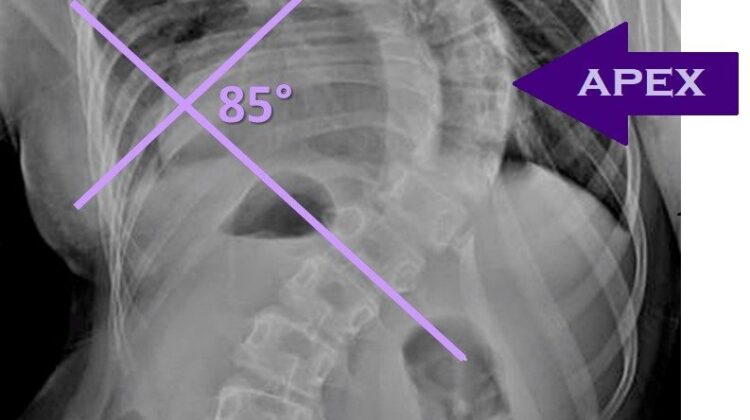

زاوية كوب هي المقياس الطبي المستخدم لتحديد شدة اعوجاج العمود الفقري من خلال صور الأشعة السينية. هذا الرقم يساعد الطبيب على فهم مدى الانحناء واتخاذ القرار العلاجي المناسب.

خاصة إذا تجاوزت زاوية كوب 50 درجة

تجاوزت 40–50 درجة